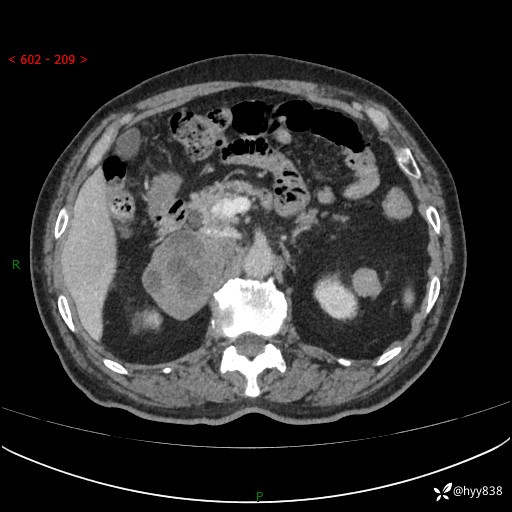

【患者信息】:76岁/男

【主诉】:检查发现右侧肾上腺占位6天

【现病史及既往史】:患者6天前体检发现右侧肾上腺占位,无腰痛,无放射痛,无尿频、尿急、尿痛及肉眼血尿,无畏寒、发热,无恶心、呕吐,今为求进一步治疗,遂来我院就诊,门诊拟“右侧肾上腺占位”收住入院。 起病以来,患者精神、饮食、睡眠可,大小便如常,体力体重无明显变化。

【检查】:肾上腺CT平扫+增强